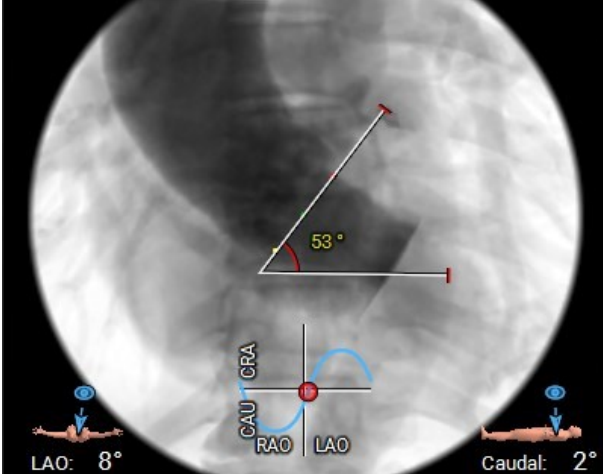

主动脉瓣环夹角:53°

患者为老年男性,合并慢性阻塞性肺疾病、胸腔积液及陈旧性脑梗,外科手术风险高。主动脉瓣重度狭窄及合并反流,瓣口面积小,术中跨瓣有一定难度。术中采用局麻方式,降低麻醉风险,计划采用25mm球囊进行预扩张,根据预扩张情况选择25mm/28mm的杰成主动脉瓣膜,植入瓣膜后根据瓣膜形态及血流动力学参数决定是否进行后扩张。患者左冠开口高度偏低,为9.6mm,杰成瓣膜总体冠脉闭塞风险较低,但术中仍需评估冠脉风险。另主动脉瓣环夹角53°,存在横位心,预估手术难度较大,术中需注意器械同轴性。

主动脉瓣环夹角:56°